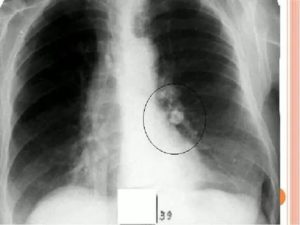

Опасны ли небольшие кальцинаты.Важно! Даже кальцинаты малого размера (на фото) в правом легком, также, как и в левом, способны становится первичным фактором, который повышает риски возникновения онкологических заболеваний и туберкулеза.

Кальцинаты определяются при проведении флюорографии или рентгена грудной клетки. На рентгеновских снимках они округлой формы с чёткими границами, на флюорографии фиксируются затемнения определённых участков паренхимы (это говорит о перенесённом воспалительном процессе в органе).

Чаще всего уплотнения расположены вблизи рёбер. Это обозначает, что кальцинаты отложились в корнях лёгких. На снимке образования дают тень с округлёнными краями.